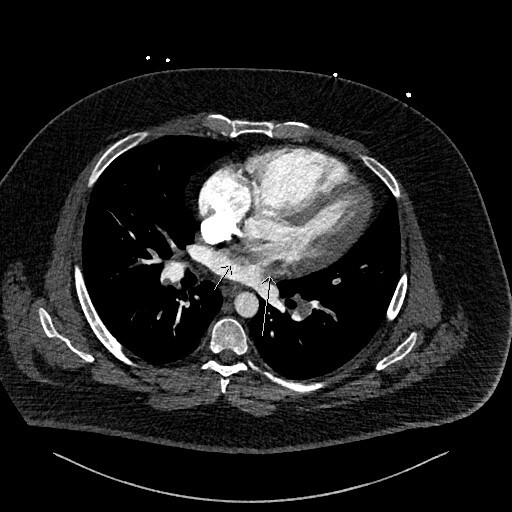

Figure 2 is an axial slice which shows a well-defined, round, homogenous and low attenuation filling defect (long white arrow) in the right atrium (RA) positioned adjacent to the interatrial septum (IAS). The filling defect is visible in the RA even despite the contrast mixing artefact in the RA chamber, the aforementioned features indicated the presence of a structure within the RA chamber, in this instance thrombus.

Figure 3 is the axial slice below and shows an elongated low attenuation and homogenous structure extending across a defect in the IAS into the left atrium (short arrow) and when viewed in contiguous slices was inseparable from the RA filling defect. This represented intracardiac thrombus in transit (ICTIT). There were further low attenuation, homogenous and well defined filling defects (medium white arrow) in the left atrium (LA). The radiologist also noted that the right heart chambers were enlarged compared to the left, and that both the IAS and interventricular septum (IVS) were inversely bowed toward the left – these are CTPA features that can indicate elevated right heart pressures and therefore right heart strain in the clinical context of PE.